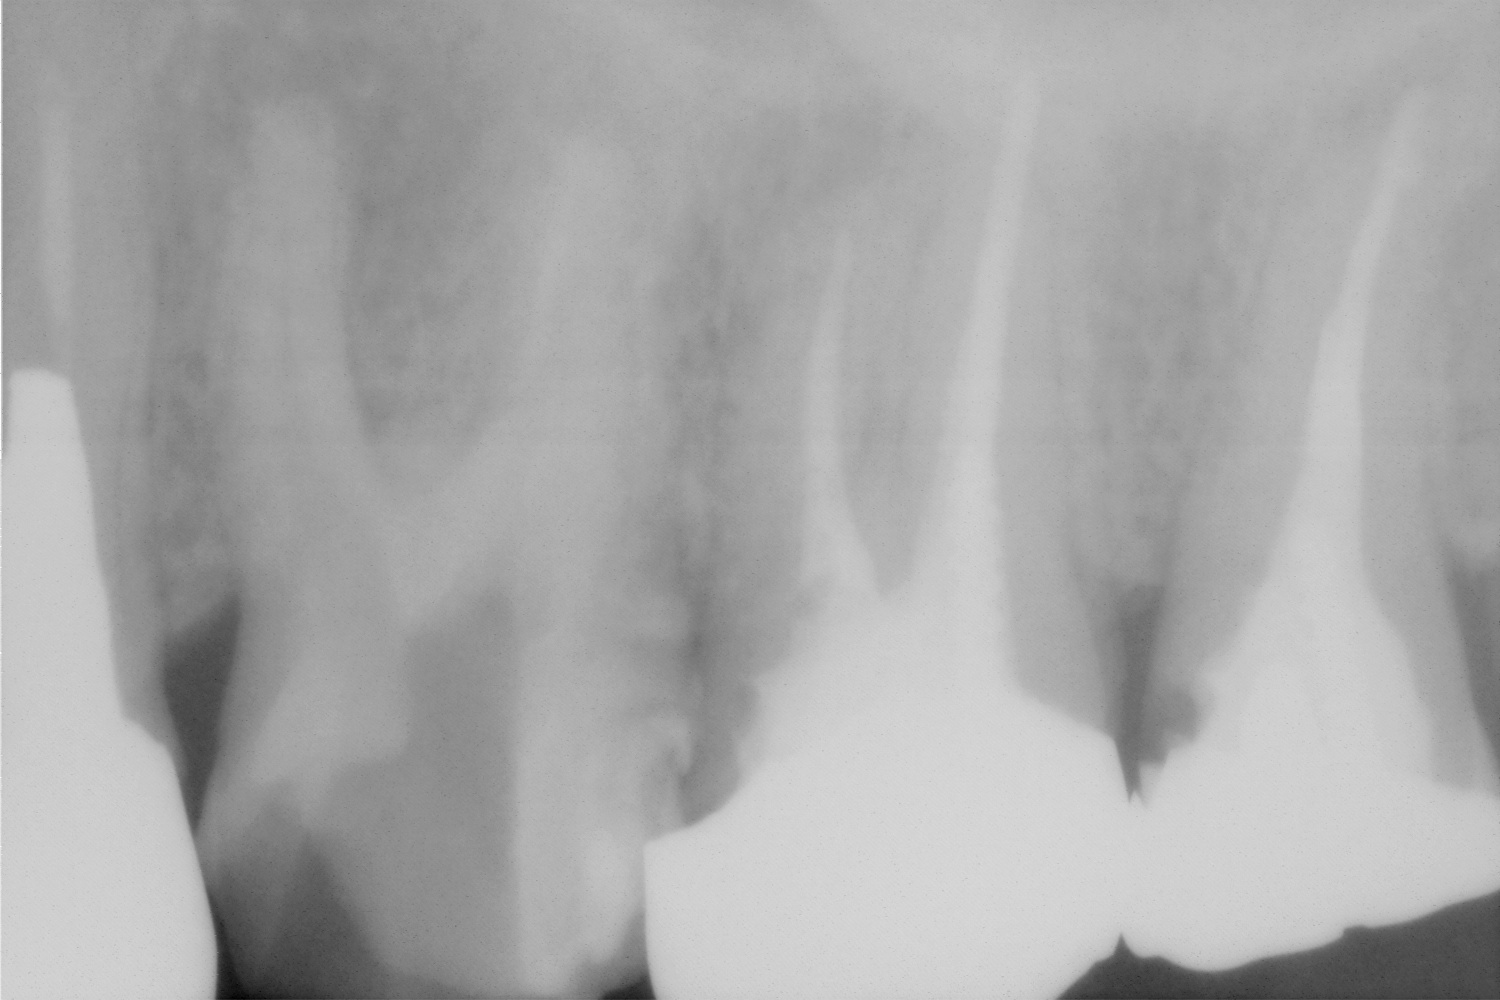

投稿日: 2013年2月26日2013年5月12日根管治療左上6、マイクロスコープをつかって 術前 左上の6番近心頬側根に何かあります。そこそこ、深く細いのですが、なんとか、除去し、治療を続けました。この根管は腫れやと痛みの原因になっていたので、除去できなければ、抜歯もしくは抜根等の外科処置もしくは抜歯が必要でした。 術中 無事に除去できました。レントゲンからわかるように、無駄な拡大もおこなっていないと思います。